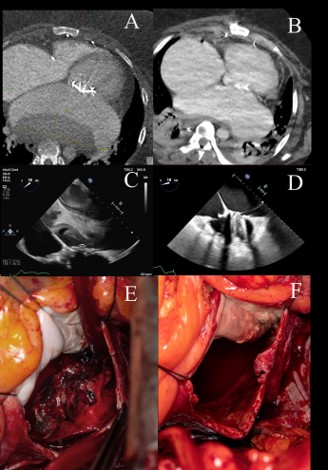

On arrival, recurrent VT was terminated with additional amiodarone boluses. CT confirmed LA mass compressing the esophagus and descending aorta (Figure 1A). Following multidisciplinary consultation, she consented to surgical excision via redo median sternotomy, entering the left atrium just anterior to the left pulmonary veins. Preoperative Transesophageal Echocardiography (TEE) showed preserved left ventricular ejection fraction (60%), biatrial enlargement, and large echodensity in posterior LA (Figure 1D). Intraoperatively, substantial nonadherent thrombus was excised (Figures 1B & 1C). Remarkably, the mechanical valve remained free of thrombus and continued to function optimally. Admitting blood cultures remained negative. She was discharged on postoperative day 30 on warfarin (Figure 1E).

Figure 1: (A) CT demonstrates significant cardiomegaly, with a non-mobile filling defect measuring 12 × 4 cm in the axial plane. (B) Resolution of the thrombus is observed on follow-up CT imaging. (C) Preoperative TEE reveals a prominent echodensity surrounded by dense spontaneous echo contrast indicative of thrombus. (D) Postoperative TEE confirms the absence of thrombus within the left atrium. (E) The atrium was surgically entered anterior to the left pulmonary veins, intraoperative imaging revealing the extensive thrombus that was encountered. (F) After removal of the thrombus, intraoperative imaging reveals an enlarged left atrium without residual thrombus.